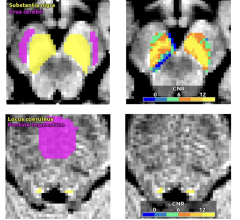

May 6, 2024 — GE HealthCare has announced the unveiling of its SIGNA MAGNUS[i], an FDA 510(k) pending head-only magnetic ...